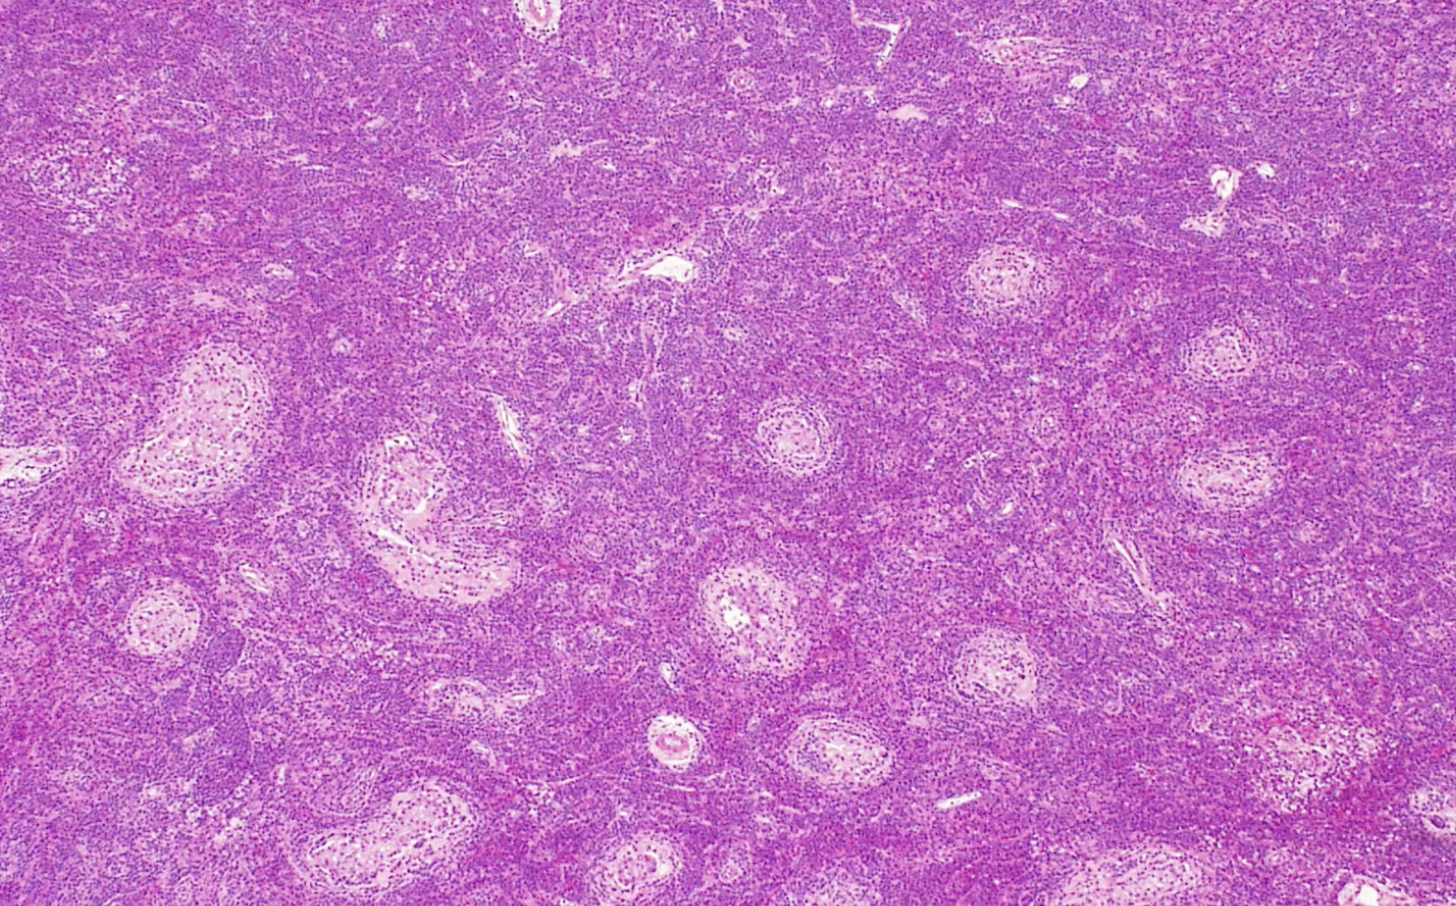

Seminoma

PLAP stain Seminoma